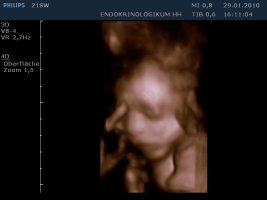

Gestern haben Sunny und ich uns erfolgreich als Versuchskanninchen für die Dopplersonographie betätigt und als Belohnung gab's 3/4D.

Das ist unser kleiner Kerl - mein Mann und ich sind hin und weg :love1

Anhänge

• 10-01-29-160926_21SW_20100129_161354_0001.jpg

10-01-29-160926_21SW_20100129_161354_0001.jpg

26,6 KB · Aufrufe: 416

• 10-01-29-160926_21SW_20100129_161354_0000.jpg

10-01-29-160926_21SW_20100129_161354_0000.jpg

26,4 KB · Aufrufe: 411